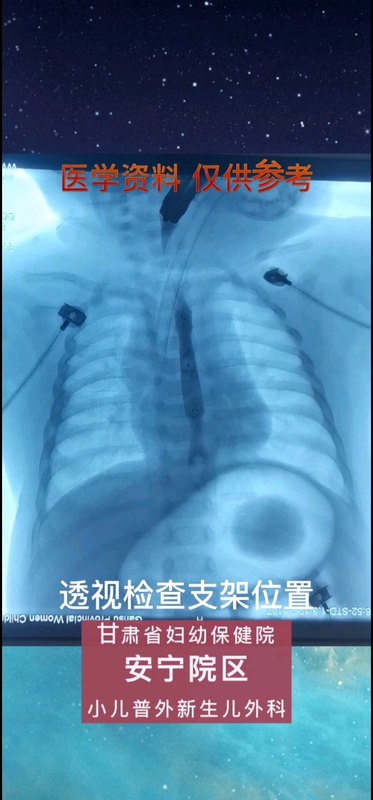

小兒外科